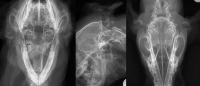

Vertical ear canal ablation is a procedure that the upper ear canal (vertical) is removed and a new ear opening is created. It can be performed when the entire vertical canal is diseased but the horizontal canal is normal.